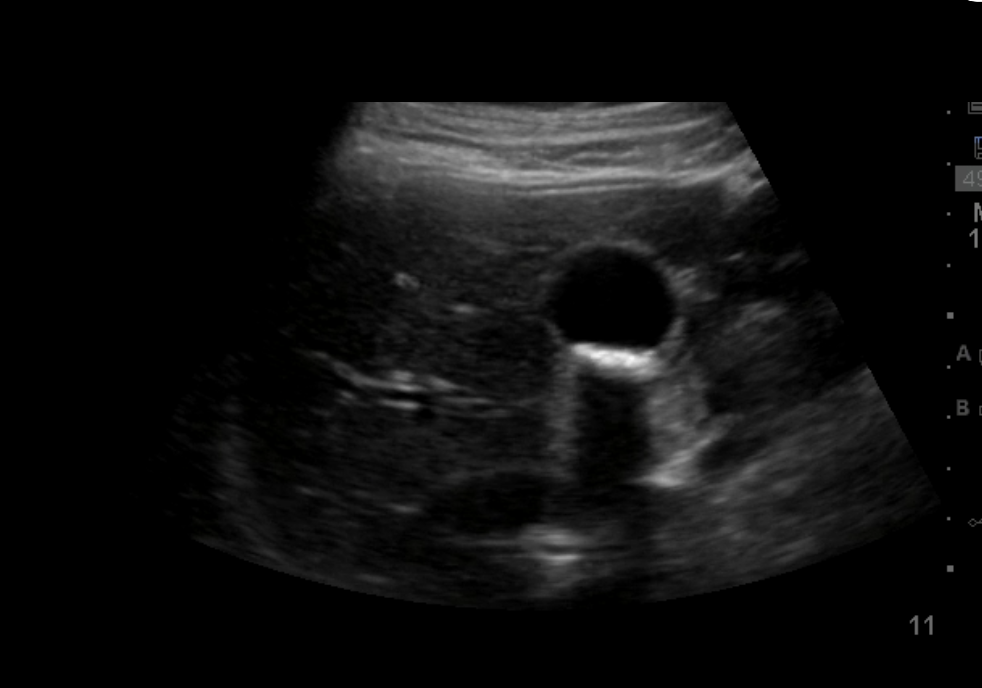

What artifact is illustrated here? (Hint: structure in thorax noted beyond the diaphgram)

Posterior acoustic enhancement – certain media allow efficient propagation of the ultrasound waves, increasing the transmission of the ultrasound wave; the tissue behind the media appears more echogenic.